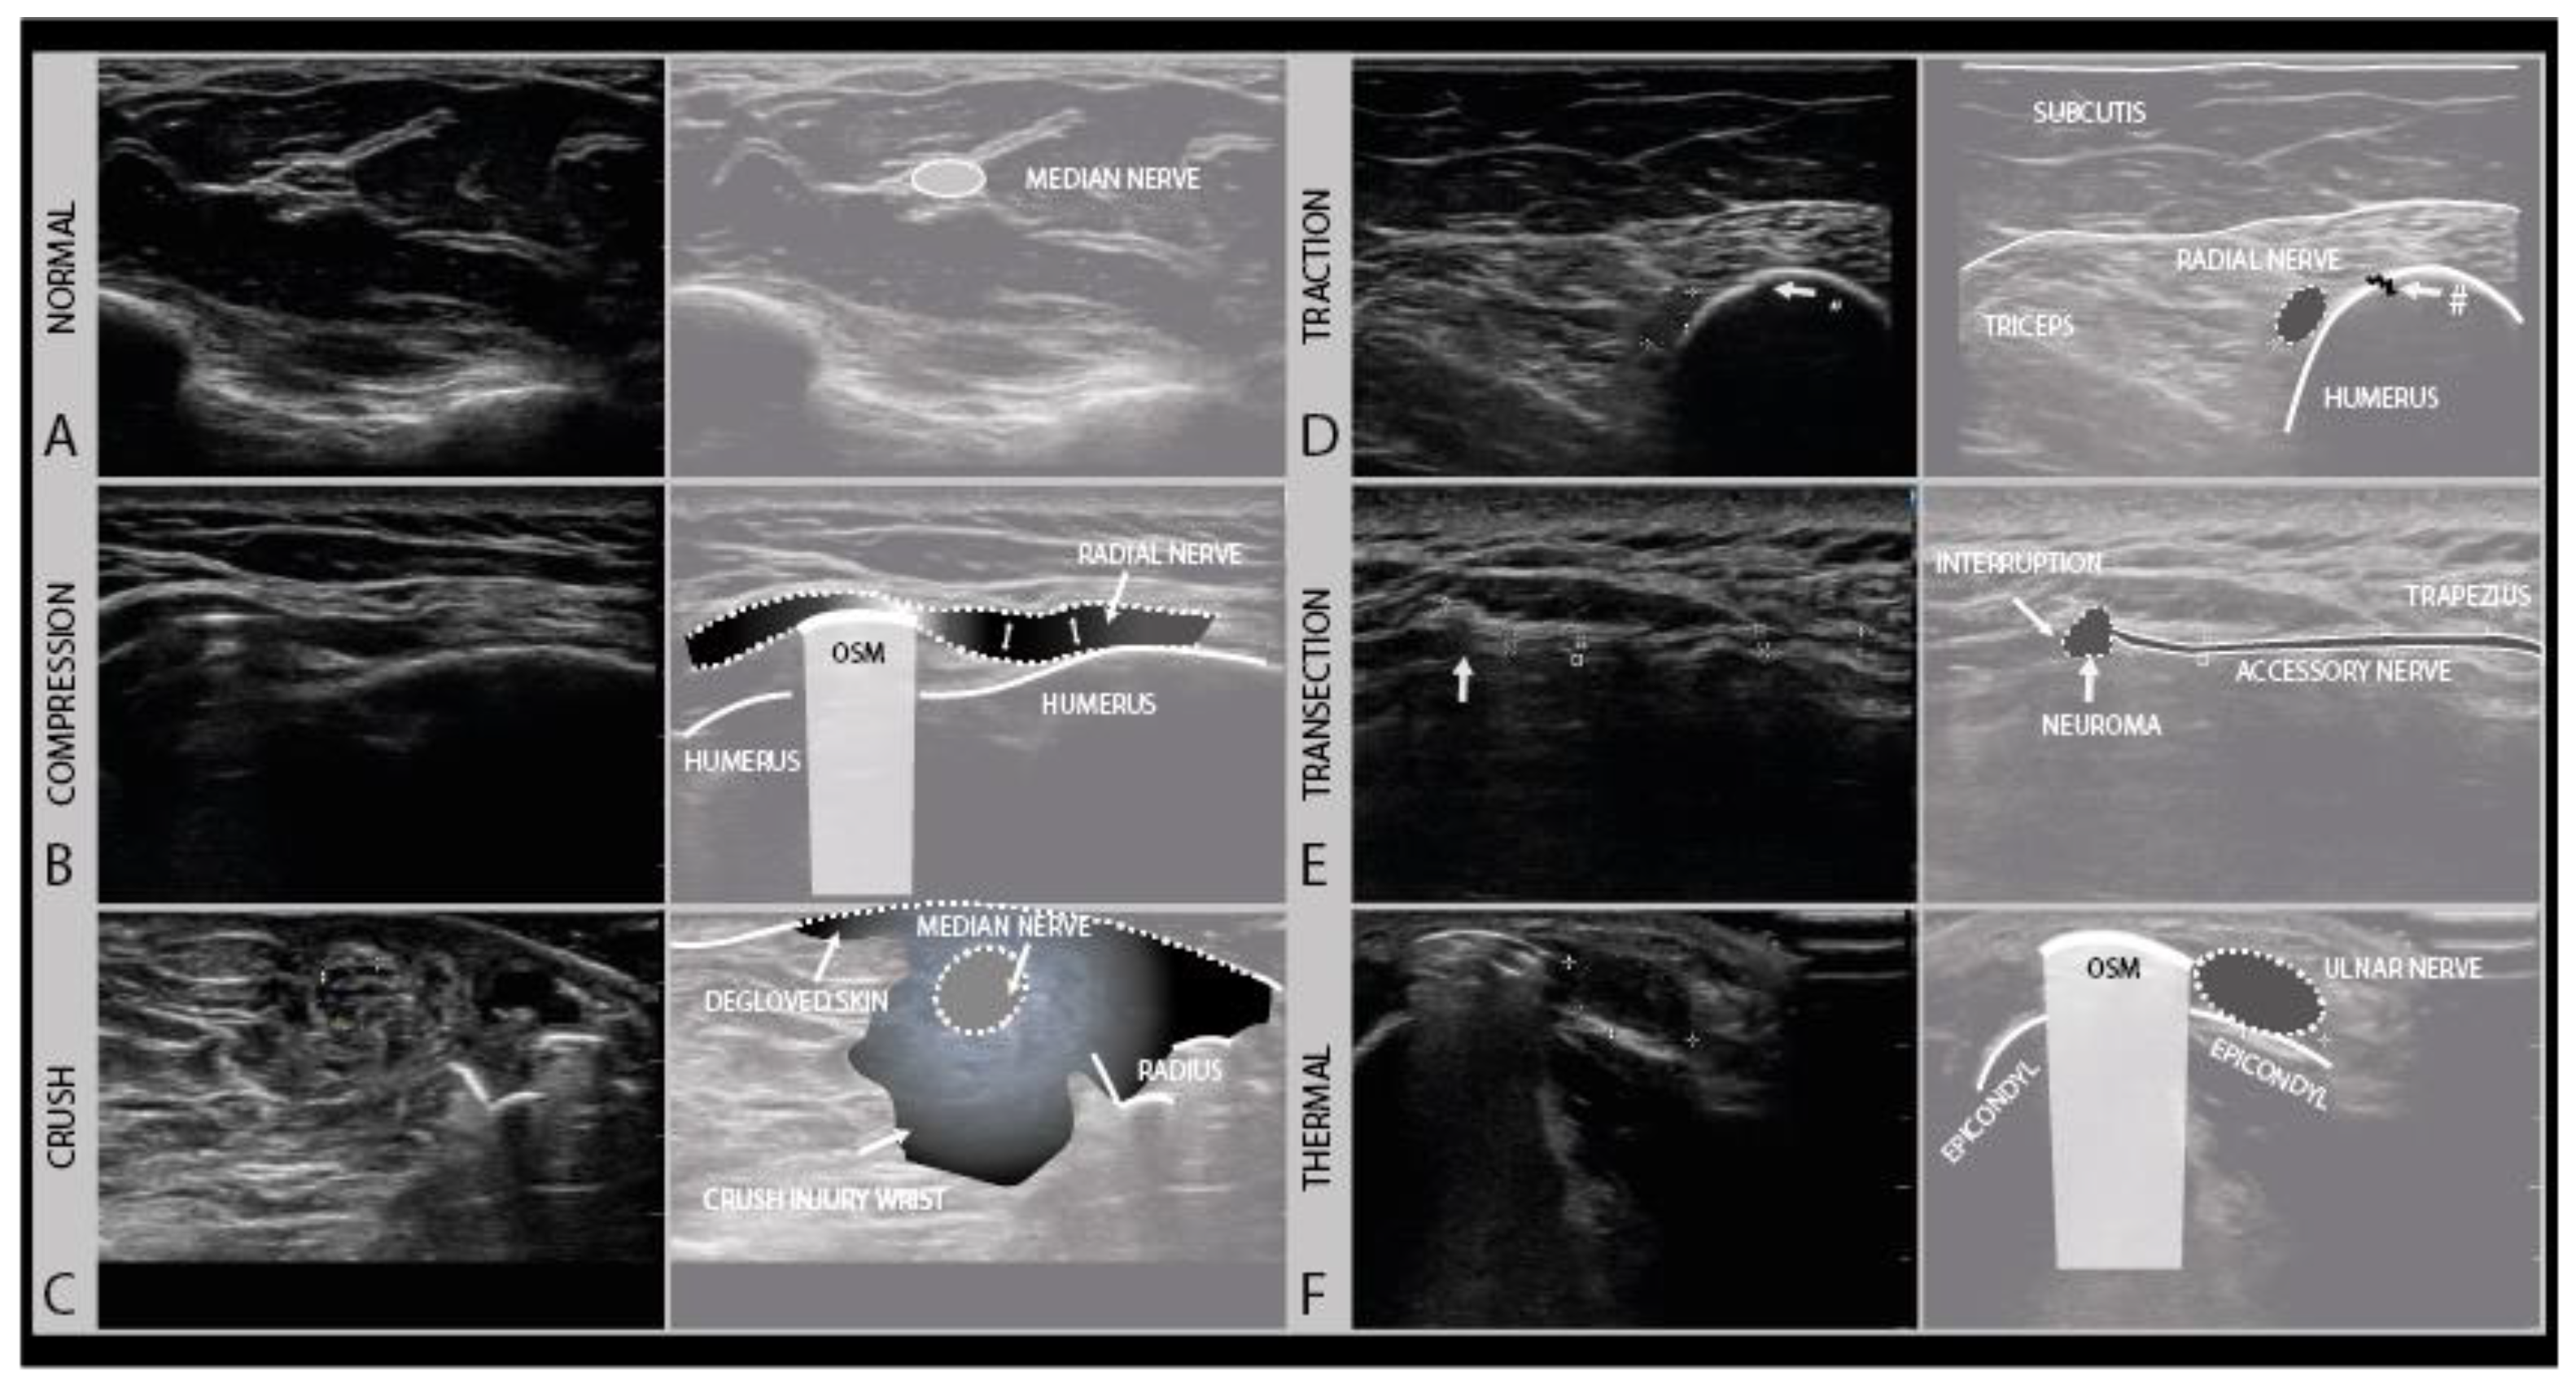

An important aspect for choosing the right therapeutic procedure and thus influencing the prognosis of a nerve injury, is to differentiate between patients with higher Sunderland grade intraneural damage or even the transection of a nerve versus a less severe lesion with preserved nerve continuity and good regenerative potential. To categorize a lesion as major or minor based on imaging (Figure 6), a few typical sonomorphologic signatures can be used, that include the fascicle swelling and hypoechoity of the nerve, the absence of a normal fascicular pattern, and the continuity assessment to detect partial or complete nerve severance with the presence of neuronal stump [28,29].

Figure 6.

Examples of different degrees of axonal damage. Case 1 (A): median nerve swelling following local trauma (fracture), fascicles intact, full recovery without surgery (Sunderland II). Case 2 (B): heterogeneous lesion of the sciatic nerve (peroneal part) of a 19-year-old boy after a scooter accident. Case 3 (C): sciatic nerve damage (Sunderland III) in a 9-year-old girl after a severe car-accident (high-frequency 9–18 MHz). (Intraoperative image kindly provided by PD. Dr. F. Lassner). Case 4 (D): iatrogenic median nerve lesion with loss of nerve continuity (Sunderland V) in a 53-year-old man after arthroscopy of the elbow joint (high frequency 19–24 MHz).

In pure neurapraxia, a Sunderland grade 1 and the least severe lesion, there are either no pathologic findings on ultrasound or just a mild swelling of the nerve with an intact fascicular pattern. A Sunderland grade 2 injury is slightly more severe with axonal damage, and also shows clearly enlarged cross-sectional areas of affected fascicles and nerves at the lesion site because of axonal swelling and edema. Higher grade damage like in patients with Sunderland grade 3 and 4 lesions shows a loss of the normal nerve architecture and echotexture with a disruption of the fascicular pattern and often sizeable hypoechogenic enlargement of the nerve. The more extensive the loss of the normal nerve architecture, the higher the chance that the nerve will develop intraneural fibrosis that hampers or prohibits recovery. For these lesions, a subdivision of the Sunderland system has been described by Millesi [30]. A Sunderland grade 5 lesion shows a transection of the nerve with a loss of nerve continuity. An overview of the nerve injury classification can be found here: https://en.wikipedia.org/wiki/Peripheral_nerve_injury_classification.

Compression injuries can either be acute or chronic. Acute compression injury, such as a peri-operative ulnar compression neuropathy, typically presents with transient paresthesia, numbness and accompanying weakness that recover in weeks. Chronic compression, e.g., carpal tunnel syndrome, is often a progressively worsening condition that persists without proper intervention. Clinically, symptoms start with paresthesia and often also pain, and progress over time to hypesthesia and muscle weakness, depending on the extent of axonal damage [33]. In the case of nerve entrapment, a focal area of nerve enlargement can be seen just proximal to the site of compression. Ultrasound not only helps with localizing the compression site but could also help in identifying its cause. An example of such nerve entrapment, caused by osteosynthesis material in this patient, is shown in Figure 7B. In this case, the radial nerve shows the focal enlargement just proximal to the screw where it is compressed. In addition to a CSA increase, this caliber change can be appreciated quite well in the longitudinal images. When entrapment is severe or chronic, an associated loss of the internal fascicular architecture can be observed as well.

Figure 7.

Examples of different trauma types. The normal transverse aspect of a median nerve in the forearm (A). Local compression injury of the radial nerve by local osteosynthesis material (OSM). Focal enlargement of the nerve diameter proximal to the lesion site can be seen (B). Crush injury of the median nerve at the level of the forearm with surrounding crushed subcutaneous tissue and degloved skin (C). Traction injury of the radial nerve after humeral fracture (#). Swollen and hypoechoic aspect of the radial nerve (D). Iatrogenic transection injury of the accessory nerve after resection of a local lipoma. A stump neuroma can be seen at the site of nerve injury, with a loss of continuity. (E). Swollen and hypoechoic ulnar nerve after thermal injury (hot K-wire) at the level of the medial epicondyle with in situ osteosynthesis material (F).

The initial therapy after traction injury is conservative and includes pain management, rehabilitative measures and a minimum follow up after 3 and 5 months. If conservative treatment fails, surgical exploration and reconstruction should be considered within 6 months [37,38]. Depending on the severity of the injury, the nerve will appear hypoechoic and swollen, with or without a disruption of the fascicular architecture. Figure 7D shows an example of a traction injury of the radial nerve, just proximal from a humerus fracture site. In the longitudinal images, the epineurium of the nerve can be seen to be intact.

Crush injuries occur from the traumatic compression of the nerve by blunt force, such as from the nerve and surrounding tissue being hit with a bat or ran over by car, getting caught in industrial machinery such as crushing rollers, or pinched between surgical clamps. Crush injuries can cause different degrees of nerve damage ranging all the way from neurapraxia to (partial) neurotmesis. Complete traumatic disruption with nerve transection (i.e., Sunderland grade 5) is rare, but the internal nerve structure can be badly damaged (i.e., Sunderland grade 4). Recovery follows the rules of the Sunderland grading system. Nerve ultrasound at the site of the injury will show a hypoechoic and enlarged nerve with more or less disrupted fascicle architecture and in the acute phase ecchymoses and edema of the surrounding tissues, as shown for example in Figure 7C.

4.4. Thermal Injury

4.5. Transection (“Sharp”) Injury

Complete nerve transection injuries are usually caused by “sharp” accidents, such a knife laceration, glass shard injury, bone drill or gunshot wound. Gunshot wounds, however, are complicated, as they can both damage the nerve directly, or damage the nerve with bone fragments from splintering upon impact, but can also cause severe traction/compression injury from the pressure waves that build up in the bullet trajectory or the subsequent compartment syndrome these pressure changes cause. After complete nerve transection (i.e., Sunderland grade 5, neurotmesis), the distal segment of the nerve will undergo Wallerian degeneration, and there is no chance of recovery across the gap as the proximal and distal nerve ends typically retract. In transection injuries, the nerve ultrasound can be used in the acute setting to reveal the discontinuation of the nerve, often best appreciated in the longitudinal direction. The hallmark is an interruption of the epineurial sheath and the fascicles. In transverse images, the nerve and fascicles in the stumps appear enlarged and hypoechoic, and over time this architecture will become more disrupted as stump neuromas develop (Figure 7E). Surgical treatment, with neurolysis and repair or grafting is the only option for nerve recovery; if this is not possible, tendon transfers and joint stabilization by splinting or arthrodesis should be considered.